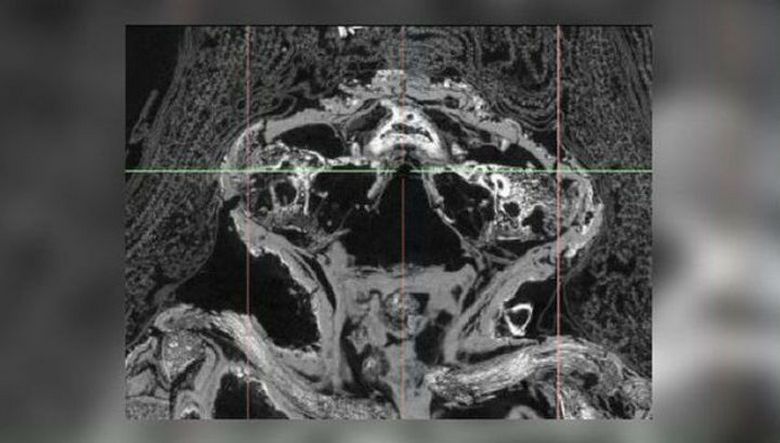

I tek nedavno je „mumija sokola“ podvrgnuta temeljitoj skeniranje (mikro-CT skeniranje omogućava naučnicima da vide, i znači, i pažljivo proučite unutrašnji sadržaj mumije, bez uklanjanja i bez kršenja njegove pogrebne građe) zajedno sa ostalim muzejima eksponati. Kakvo je iznenađenje istraživača bilo kad shvatio da ti ostaci ne pripadaju ptici, ali mrtvorođena prerano rođena beba.

Pokazalo se da to dete još pati u maternici tako rijetka bolest kao anencefalija, kod koje se ne razvijaju mozak i sam kranija koji su prouzrokovali pobačaj. Dijete je bilo oko 25 sedmica, već se formiralo tijela, udova, čak nožnih prstiju i ruku, ali gornji dio lobanje – ne. Uz to je i bolovao od urođene usne cijevi – tako zvano rascjep nepca. Još jedna stvar je iznenađujuća: zbog čega je to razlog pobačaj je mumificiran? Obično su takva “djeca” u starom Egiptu (i ne samo u njemu) samo zakopano u saksiji i to samo u najrjeđi slučajevi su se odvijali upravo onako kako vidimo – mumificiran. Navodno je dijete smatrano posebnim, a i njegovim mrtvorođenje – dostojan odlazak u svijet mrtvih …